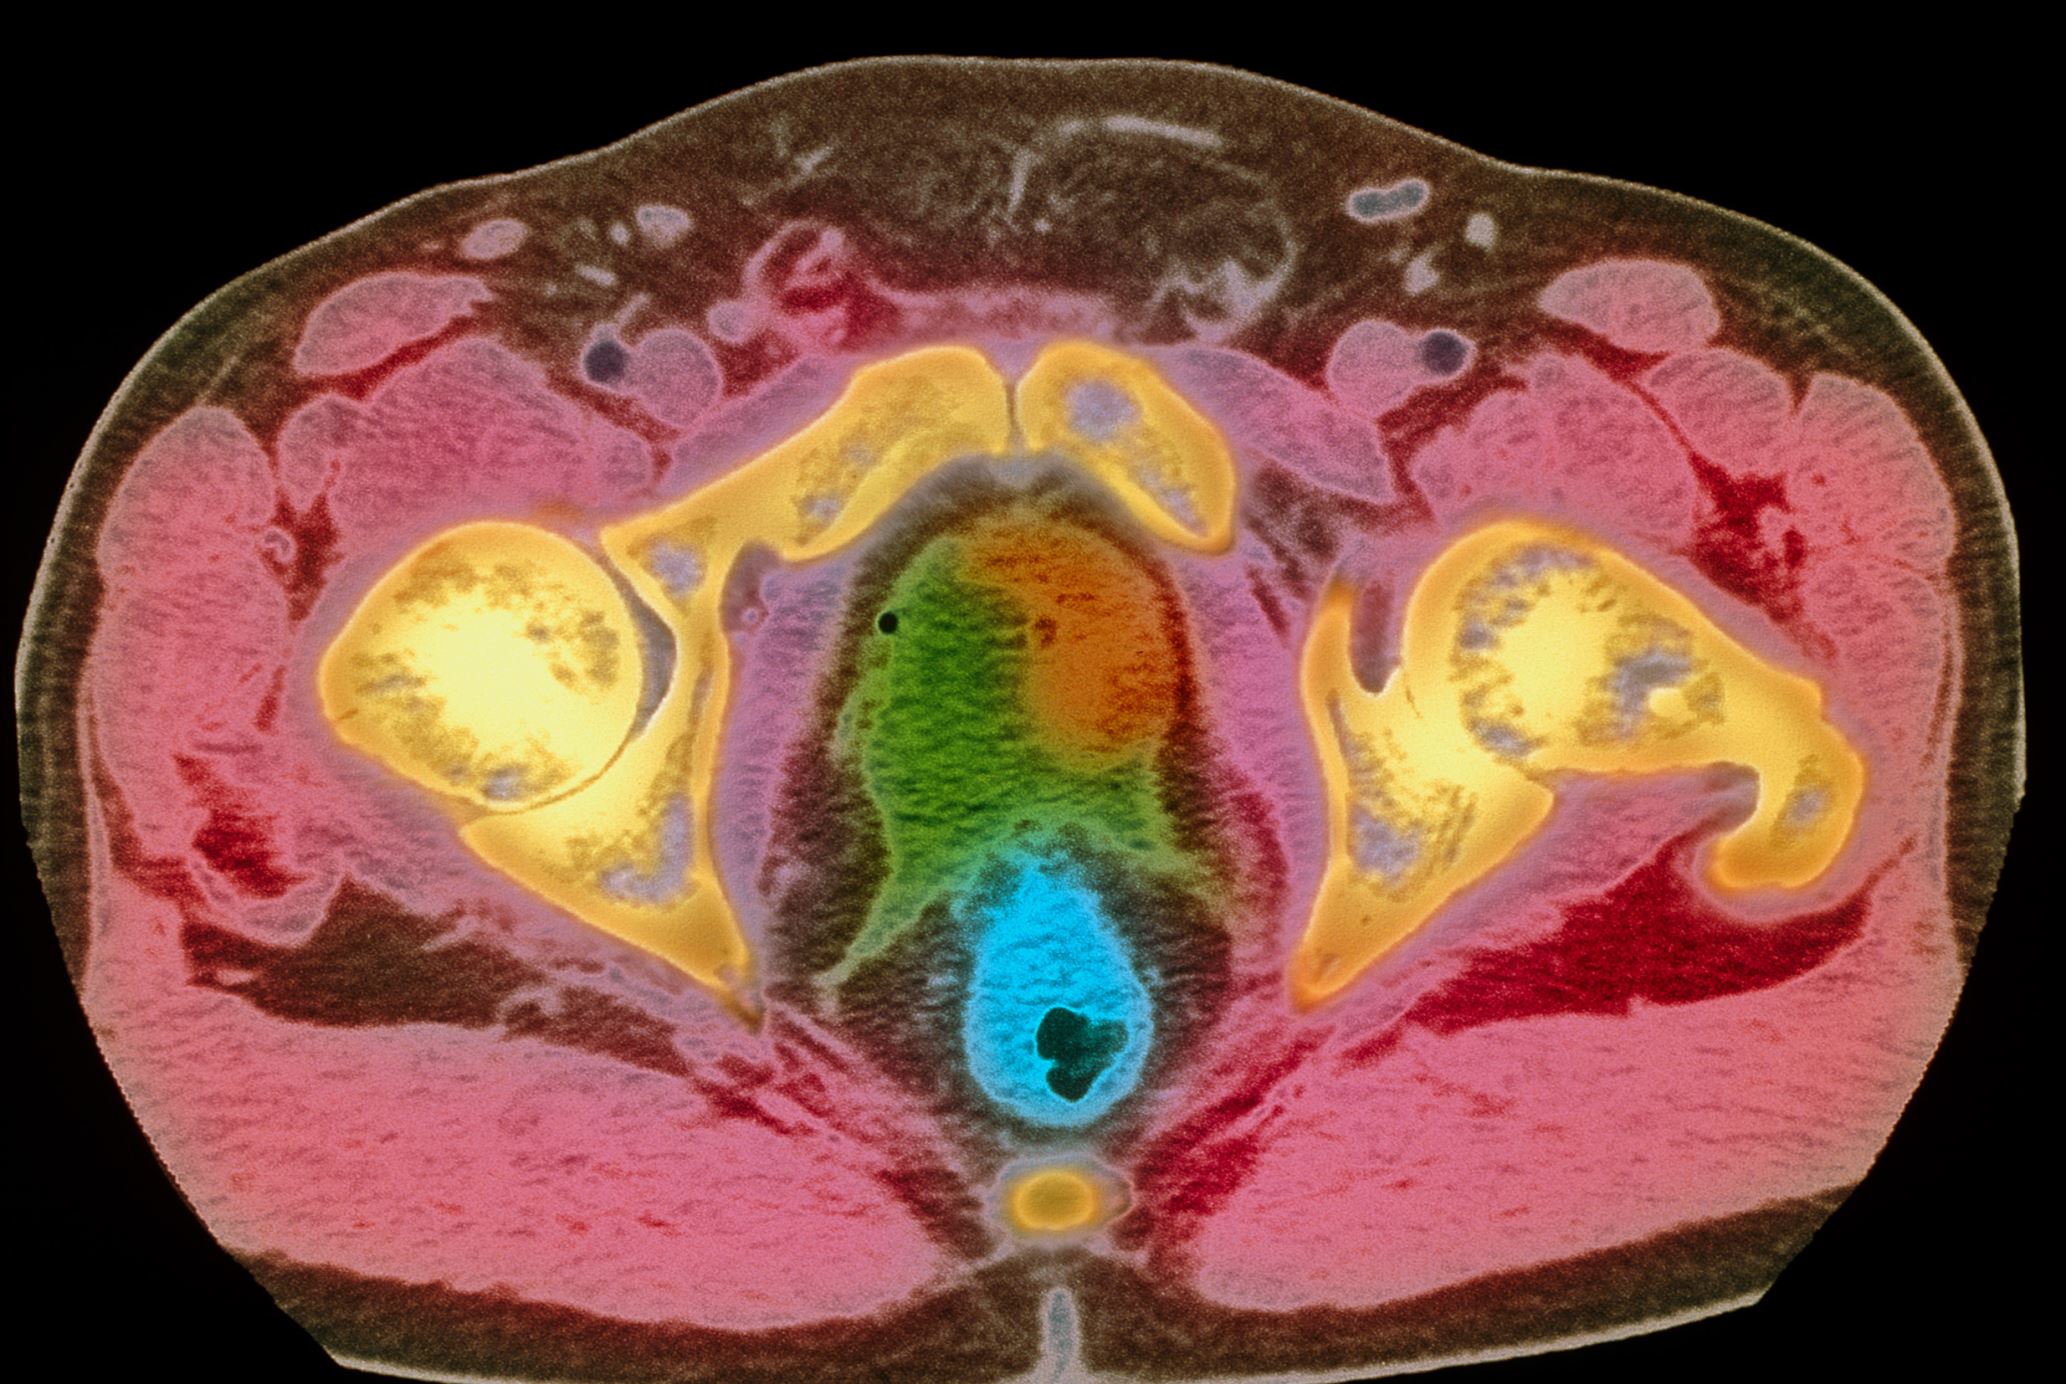

Das Prostatakarzinom ist häufigster Tumor und zweithäufigste Krebstodesursache des Mannes, jährlich versterben 15.000 Patienten. In Deutschland gibt es keine Früherkennungsprogramm - aber viel unsinnige Praxis, wie digital-rektale Untersuchungen bei jungen und PSA-Bestimmungen bei alten Männern. Eine systematische, zeitgemäße und Risiko-adaptierte Früherkennungsstrategie könnte unnötige Diagnostik und Therapien vermeiden und die Mortalität deutlich reduzieren.

© Science Photo Library

Prostatakarzinom/© Science Photo Library, Vortrag Renders/© Leo Pharma GmbH, Teaserbild Blutungsrisko managen bei Antikoagulation - Waage/© Leo Pharma GmbH, Vortrag Frankfurter Gerinnungssymposium/© LEO Pharma GmbH (Screenshot aus Vortrag), Thrombus und Patientin im Gespräch/© crevis / adobe.stock.com (Symbolbild mit Fotomodell), Berlin/© amyrxa / stock.adobe.com